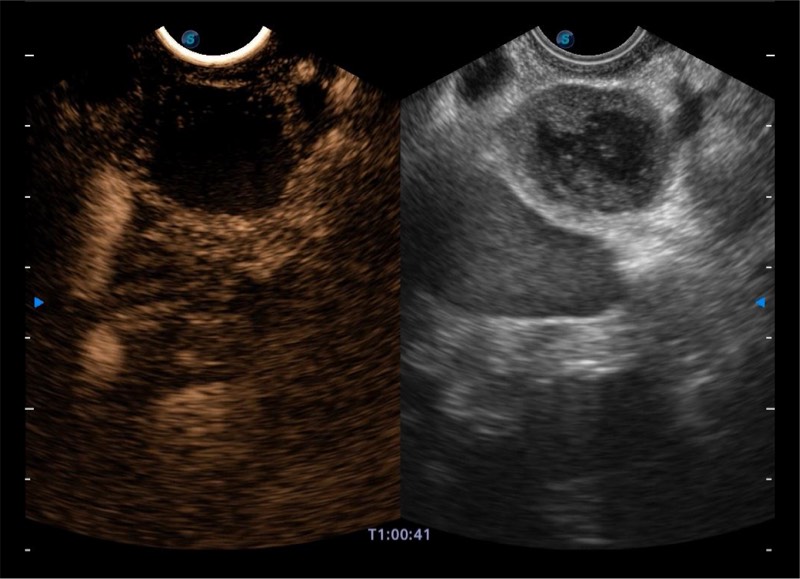

基于二十年的超声技术积累,环球UG官网提供了最新一代的独立超声主机,在提供高质量图像的同时满足多学科使用。具备常见多普勒技术并提供弹性成像、声学造影等高端影像技术。新一代传感器具有更强的抗干扰能力并减少图像伪影。